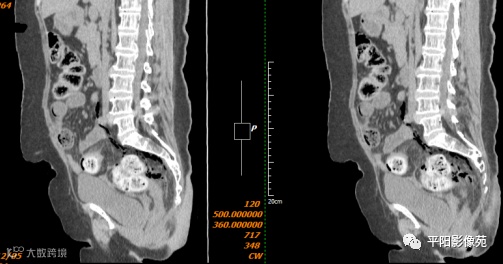

影像表现:乙状结肠前方可见不规则条状软组织密度影,边界不清,内见点状高密度;乙状结肠周围及骶前可见多发气体密度影。

术中见:腹腔内有淡红色脓液液体约200ml,聚集于下腹部、盆腔,腹膜反折上方直肠可及约8.0*8.0*8.0cm肿物,质韧,光滑,界清,局部直肠系膜坏死、色黑、有脓液及气体自系膜坏死区域溢出,伴粪臭味,横结肠、降结肠及乙状结肠内有大量干粪块。吸尽脓液,探查肝脏左右叶、网膜、腹膜均未见肿瘤及转移结节,术中诊断:直肠穿孔。遂决定行直肠切除、乙状结肠造瘘术。

标本肉眼:剖开标本可见位于腹膜反折上方约3cm处,直肠系膜侧肠壁有一约5cm纵行裂口,大量粪块经此裂口进入直肠系膜内,裂口周围直肠粘膜略有质韧、局部组织肿胀,未见明显肿瘤存在。

影像表现:主要特点是腹腔内游离气体,可见肠壁增厚,边缘模糊,周围脂肪间隙模糊不清,并见不规则片状低密度,有粪石漏出时可见结节状高密度。